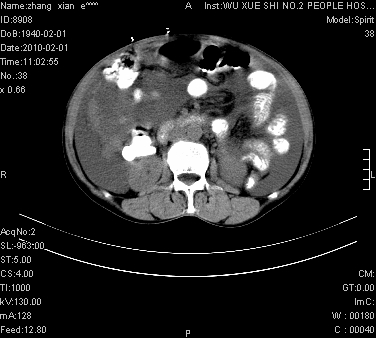

标题: CT24434:70岁 女 腹胀,腹水原因待查 [打印本页]

标题: CT24434:70岁 女 腹胀,腹水原因待查

大量腹水,脾脏囊性占位,子宫颈占位,右侧腹股沟淋巴结肿大,建议+c,先查妇科。

腹盆腔大量积液,子宫增大,子宫颈增大外形不规则,内见低密度影,膀胱后壁显示不清,右腹股沟肿大淋巴结,脾脏囊性占位,子宫颈占位,子宫颈癌?建议增强。

腹盆腔大量积液,子宫增大,子宫颈增大外形不规则,内见低密度影,膀胱后壁显示不清,右腹股沟肿大淋巴结,脾脏囊性占位,子宫颈占位,子宫颈癌?建议增强。支持!